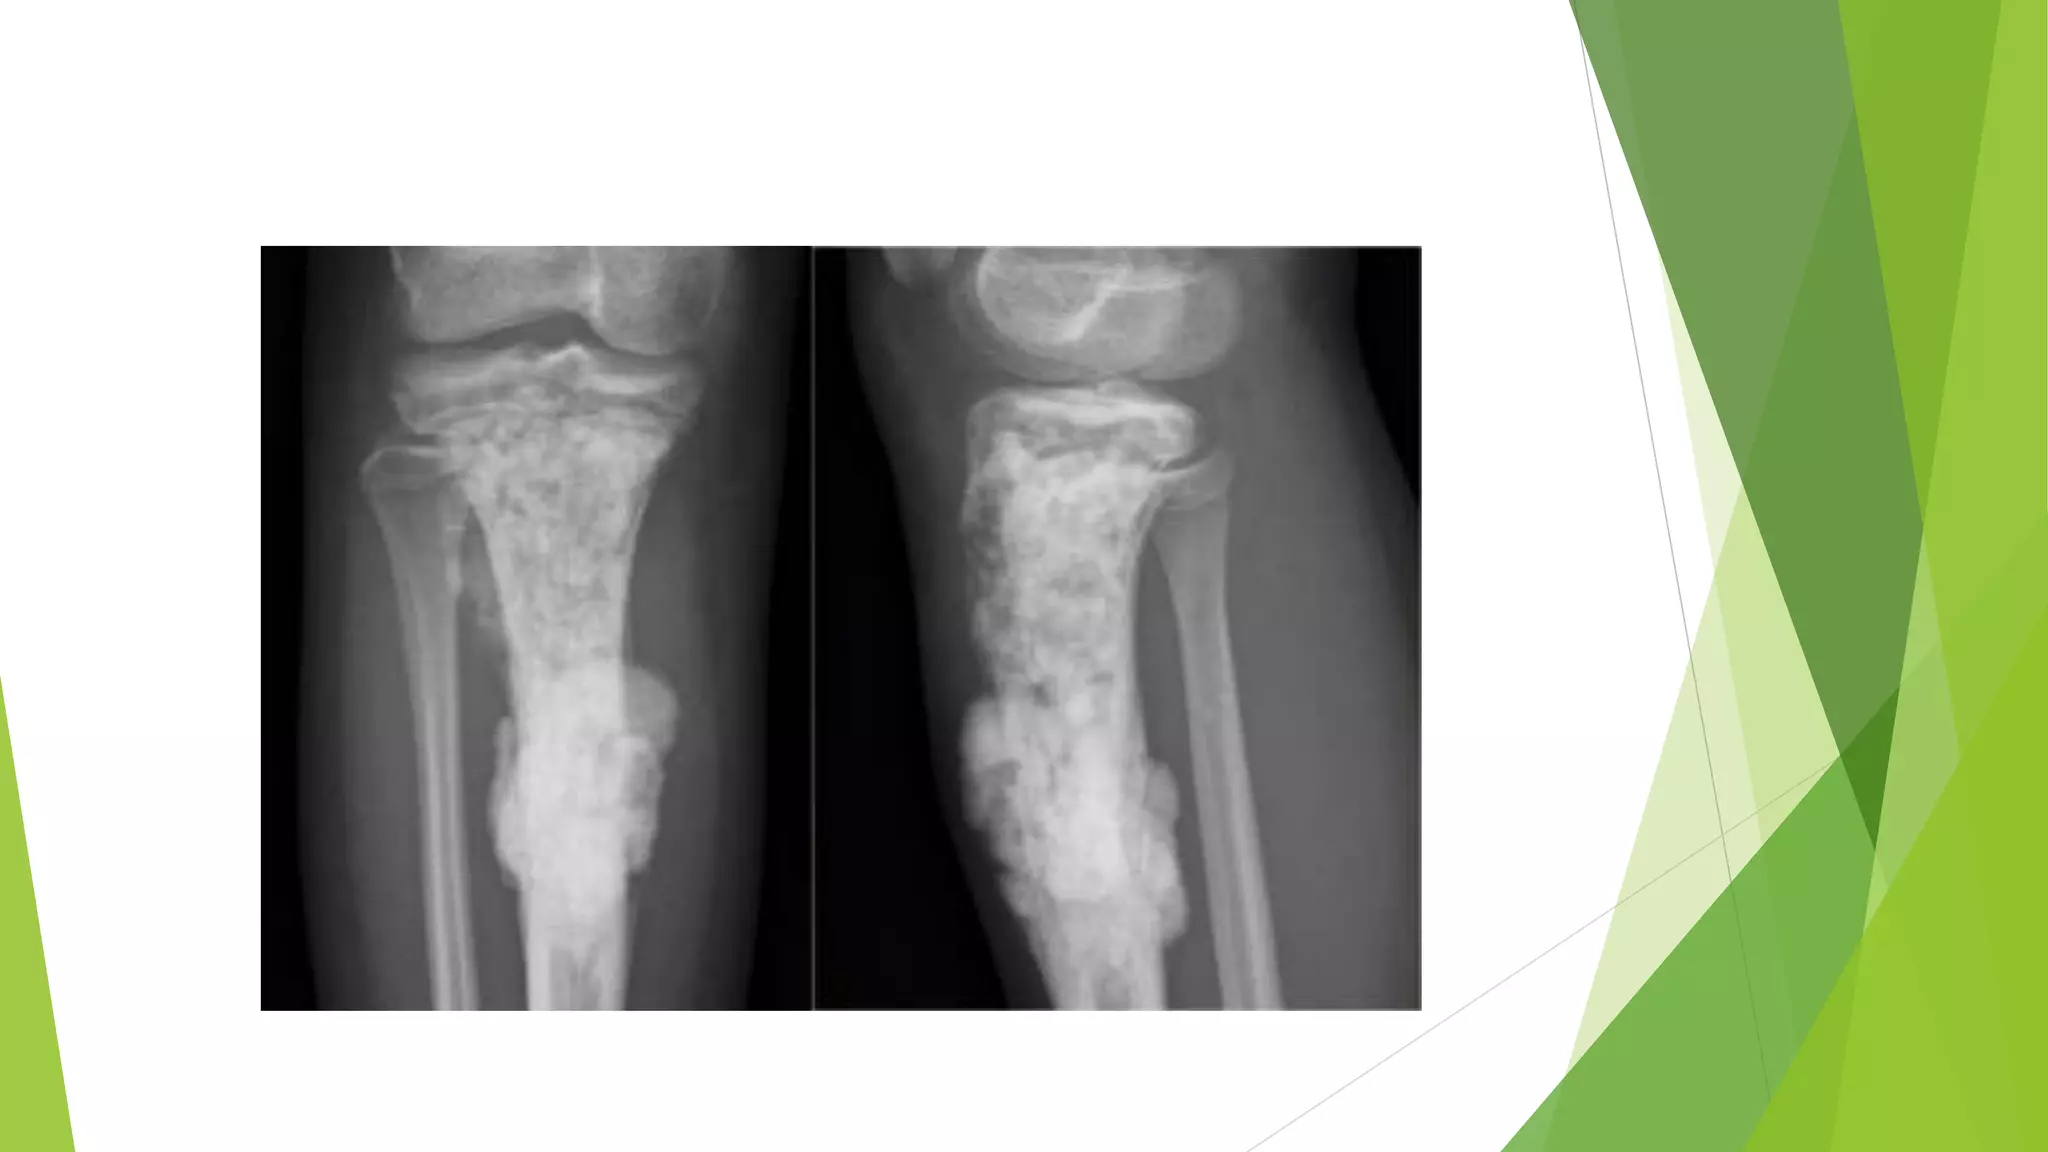

 Radiographs usually show a large, destructive, mixed lytic and

blastic mass with indistinct infiltrating margins.

 The tumor frequently breaks through the cortex and lifts the

periosteum, resulting in reactive periosteal bone formation.

 A triangular shadow on x-ray between the cortex and raised

periosteum (Codman triangle) is characteristic of

osteosarcomas. Osteosarcomas typically spread